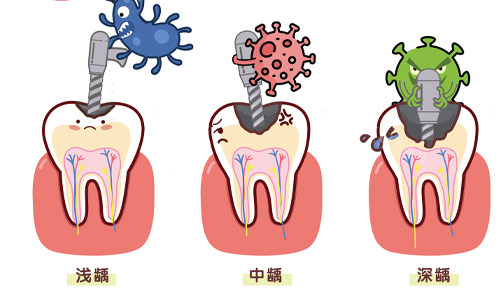

郑州快乐蜗牛口腔拥有一支特色且经验充足的儿童齿科团队。团队中的医生们都经过了系统的特色培训,具备扎实的口腔医学知识和丰富的临床经验。他们不仅擅长处理常见的儿童牙齿问题,如龋齿、牙列不齐等,还能针对不同年龄段孩子的特点,制定个性化的治疗方案。而且,医生们非常有耐心和爱心,懂得如何与孩子沟通交流,缓解孩子在看牙过程中的紧张和恐惧情绪,让孩子能够更加配合治疗。

许多孩子对看牙存在恐惧心理,特别大一部分原因是担心治疗过程会疼痛。而郑州快乐蜗牛口腔提出了“不痛治疗”的特色理念,通过可靠的技术和设备,尽可能地减少孩子在治疗过程中的疼痛感。例如,在进行龋齿填充时,采用不痛麻醉技术,让孩子在几乎没有感觉的情况下完成治疗。这种“不痛治疗”的体验,让孩子不再害怕看牙,也让家长们更加放心。不少家长反馈,孩子在快乐蜗牛口腔看牙后,对看牙的抵触情绪明显降低,甚至主动要求定期来检查牙齿。

除了常见的儿童牙齿治疗项目外,郑州快乐蜗牛口腔还提供齐全的口腔服务。包括儿童牙齿预防保健,如涂氟、窝沟封闭等,帮助孩子预防龋齿的发生;早期牙齿矫正,针对一些有牙齿不齐倾向的孩子,进行早期干预和矫正,避免问题进一步恶化;以及口腔健康教育,通过生动有趣的方式向孩子和家长传授正确的口腔护理知识,培养孩子良好的口腔卫生习惯。